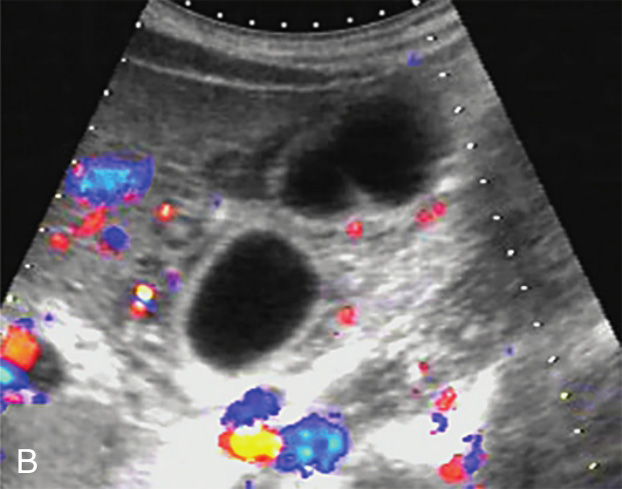

1)胆囊增大,胆囊壁弥漫性增厚,不光滑,呈“双边征”,胆囊壁内可见较丰富血流信号(图2-2-1)。

图2-2-1 急性胆囊炎常规超声图像

A.胆囊壁弥漫性明显增厚,不光滑,呈“双边征”;B.胆囊壁内较丰富的血流信号